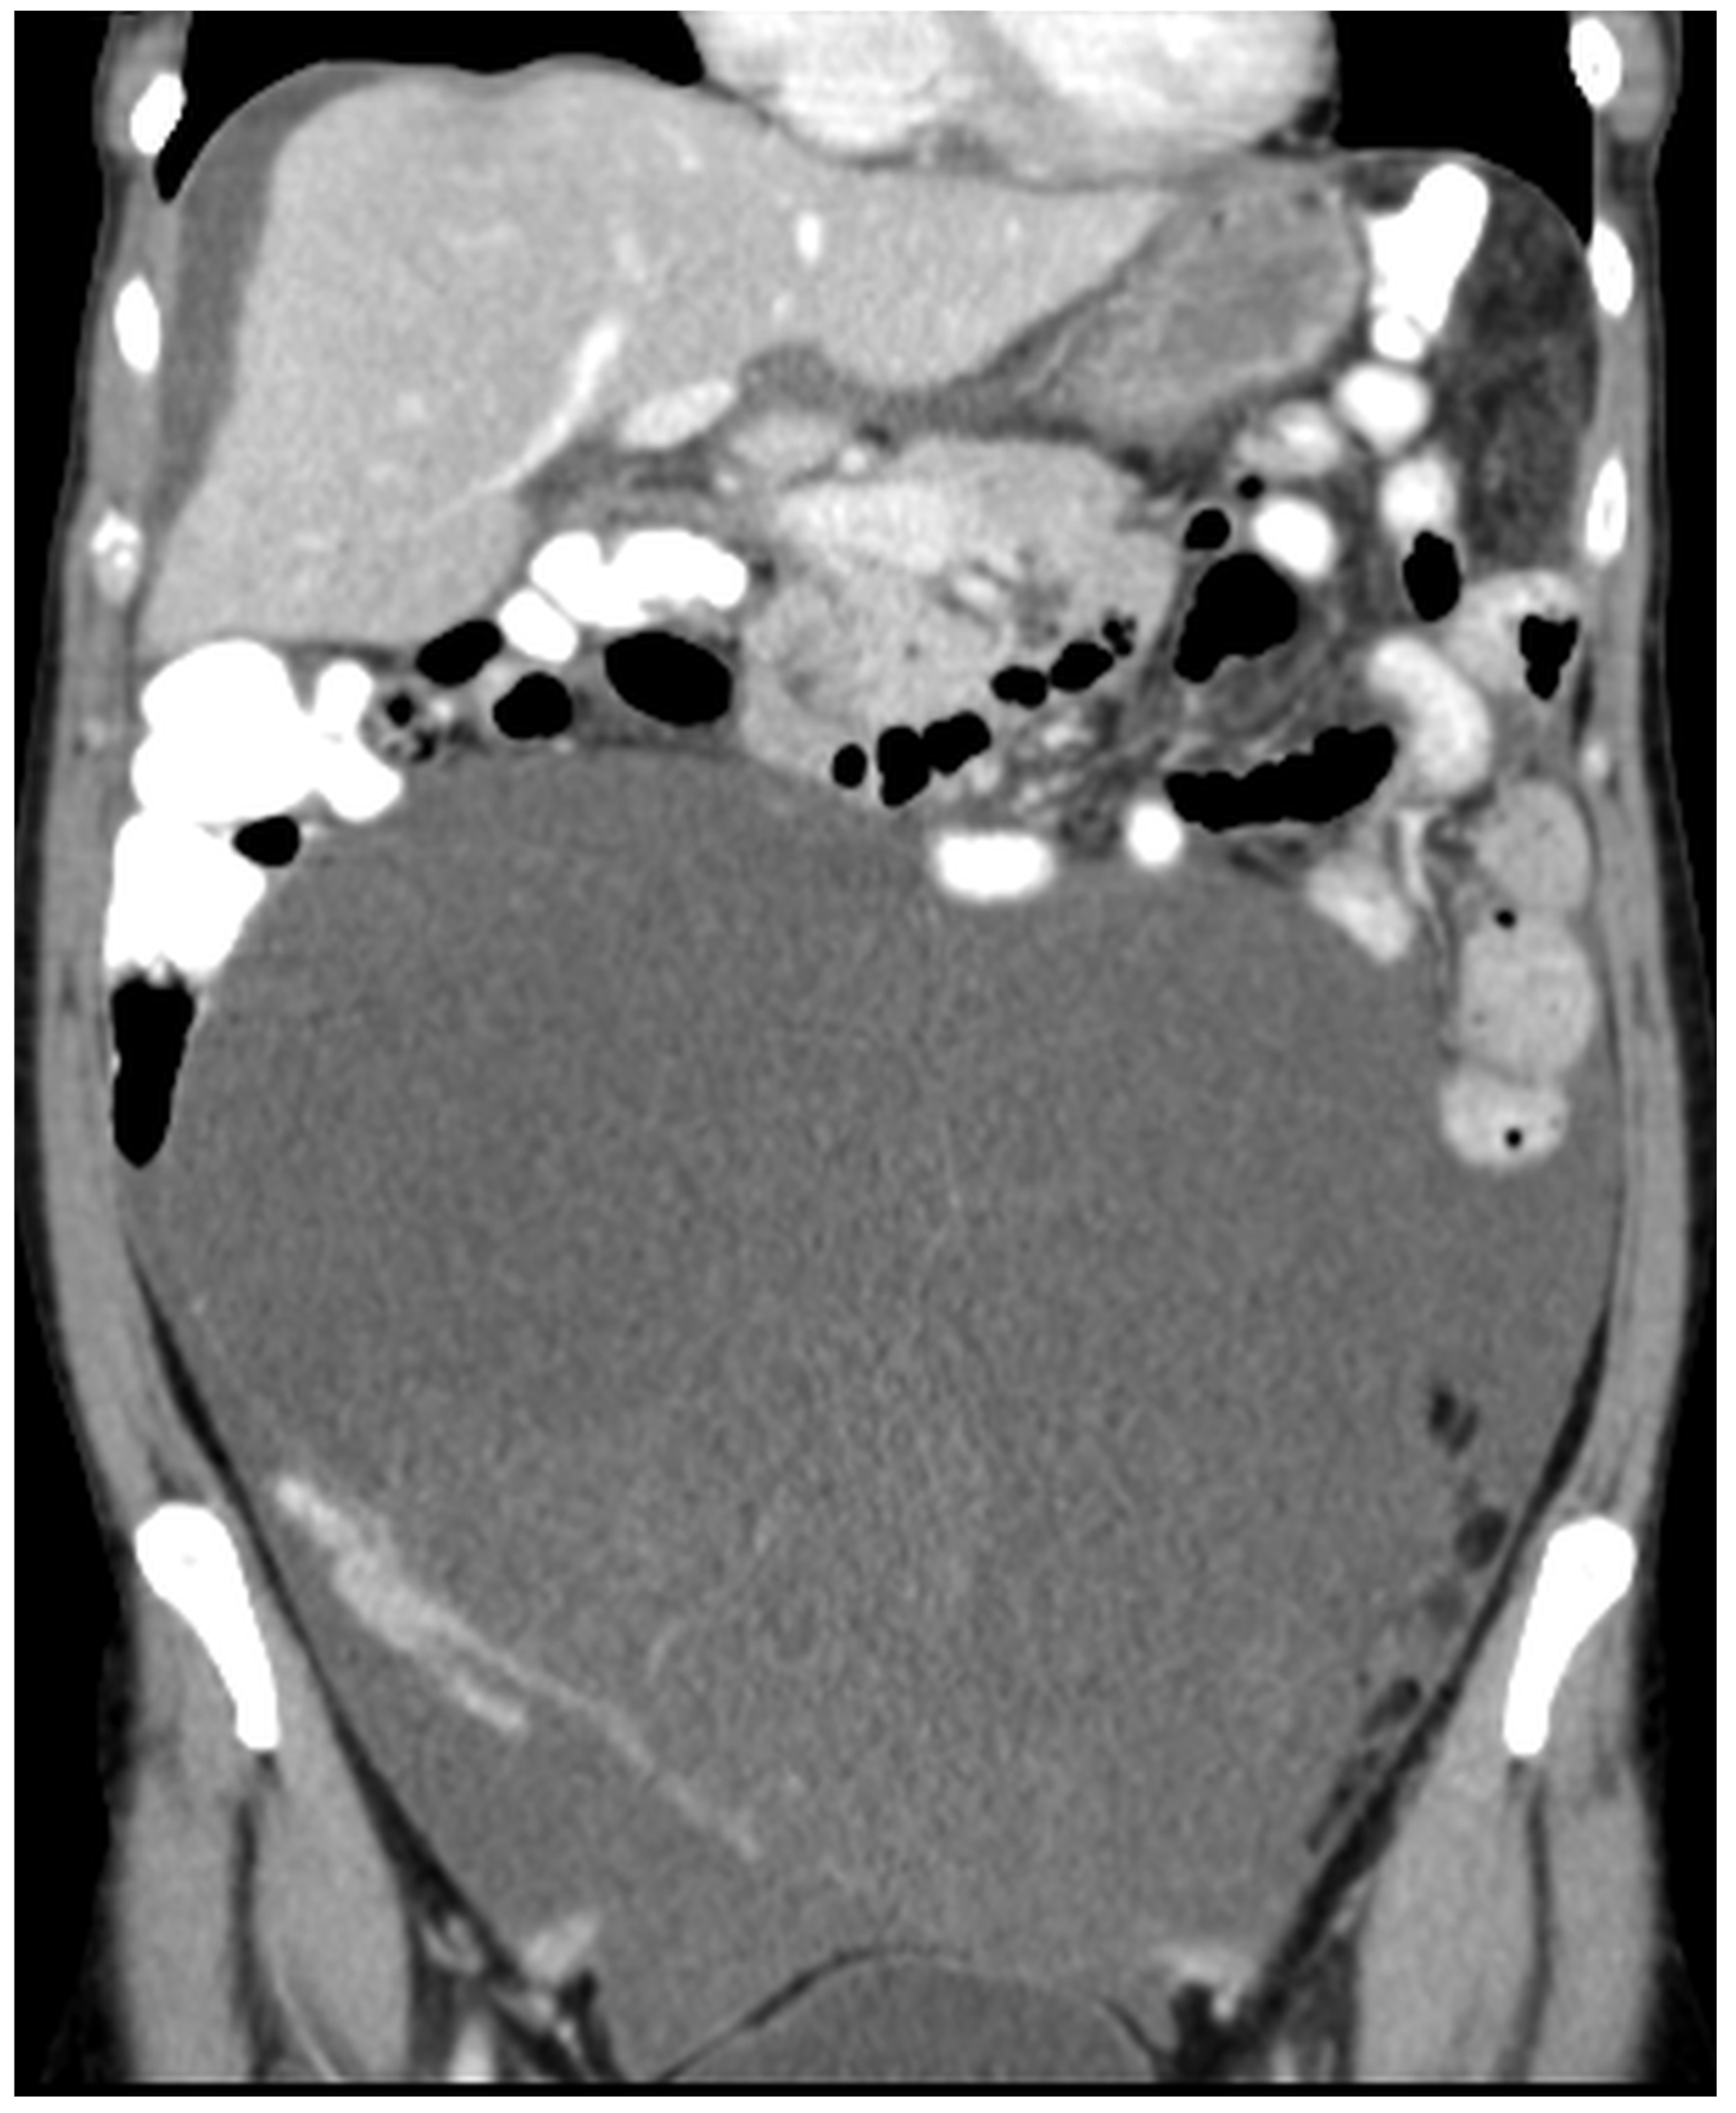

Figure 11, Figure 12, Figure 13, Figure 14 and Figure 15. Advanced stage of the disease. The abdomen is full of tumors and mucin. Typical signs are heterogeneous or hypodense masses in the form of lobules often with septa, which could be enhanced by contrast and could be associated with calcifications.

Patients with a misdiagnosed rupture of the mucocele may develop pseudomyxoma peritonei. It is characterized by the presence of an abundant gelatinous substance in the abdomen. Diffuse, progressive, and abundant mucin-containing tumor cells are typical of this disease [2] (Figure 11, Figure 12, Figure 13, Figure 14, Figure 15 and Figure 16). The interval between rupture and advanced disease is several years. In our clinical series, the interval was about 5 years. In the literature, we found a wide range of this interval from 12 months to 10 years [9,10]. The natural history of PMP revolves around the “redistribution phenomenon”, whereby mucinous tumor cells accumulate in the Douglas pouch, in the diaphragm (more on the right), and the small and large omentum (Figure 17). The small intestine is less involved [4]. Pseudomyxoma peritonei is a slowly progressing disease, which fills the peritoneal cavity over time. There are several classifications of pseudomyxoma. The most commonly used is the PSOGI classification [2]. Mucinous accumulation progresses to malnutrition, bowel obstruction, and respiratory compromise. Rarely, the tumor may spread to the pleural cavity. This has been described in 5.4% of cases. It may occur spontaneously or as a result of diaphragmatic injury during cytoreduction [8,11].

Figure 12. CT, venous phase, coronar plane.

Figure 14. CT, venous phase, coronar plane.